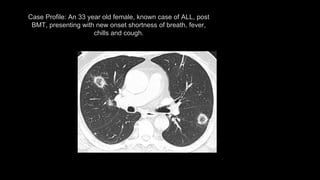

Case Profile: An 33 year old female, known case of ALL, post

BMT, presenting with new onset shortness of breath, fever,

chills and cough.